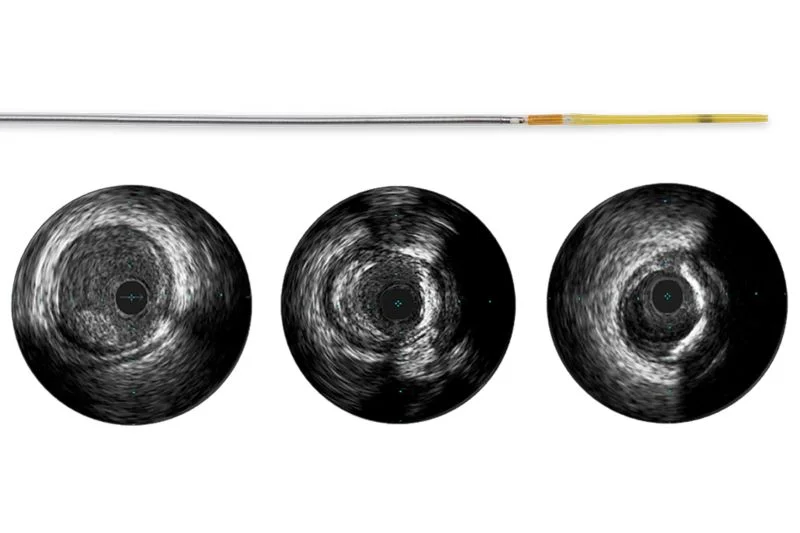

Refinity — Ротационный катетер для ВСУЗИ

Ротационный IVUS-катетер нового поколения Philips Volcano. Частота 45 МГц для максимально чёткого изображения. GlyDx-покрытие, мягкий гибкий кончик. Совместим с радиальным доступом и направляющими катетерами от 5F.

| Частота датчика | 45 МГц |

| Профиль катетера | 3,0 Fr |

| Технология | Ротационный (rotational) |